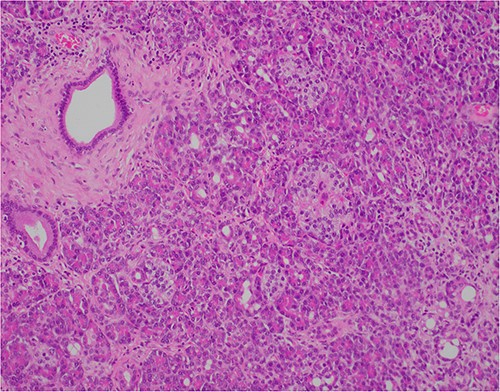

At outpatient phone clinic review 2 months post-surgery, the patient had recovered well, and his pre-operative symptoms of nausea, vomiting and pain had completely resolved. The histopathology of the gallbladder found chronic cholecystitis with cholelithiasis, in addition to a 6 mm focus of pancreatic heterotopia in the gallbladder wall. This heterotopic tissue contained acini, ducts and islet cells, classifying it as Type I pancreatic heterotopia (Figs 1–3).

×10 objective lens; showing central duct with surrounding pancreatic acini and islets, with preserved architecture.